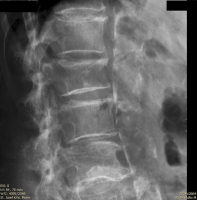

Möglichkeiten der direkten Zementinjektionstechnik bei Wirbelkörperfrakturen - Drei Fallbeschreibungen der Radiofrequenz-Kyphoplastie (RFK) mit ultrahochvikösem Knochenzement